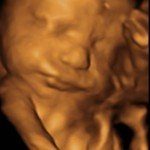

4D/5D/HD Ultrasound Gallery

Gallery